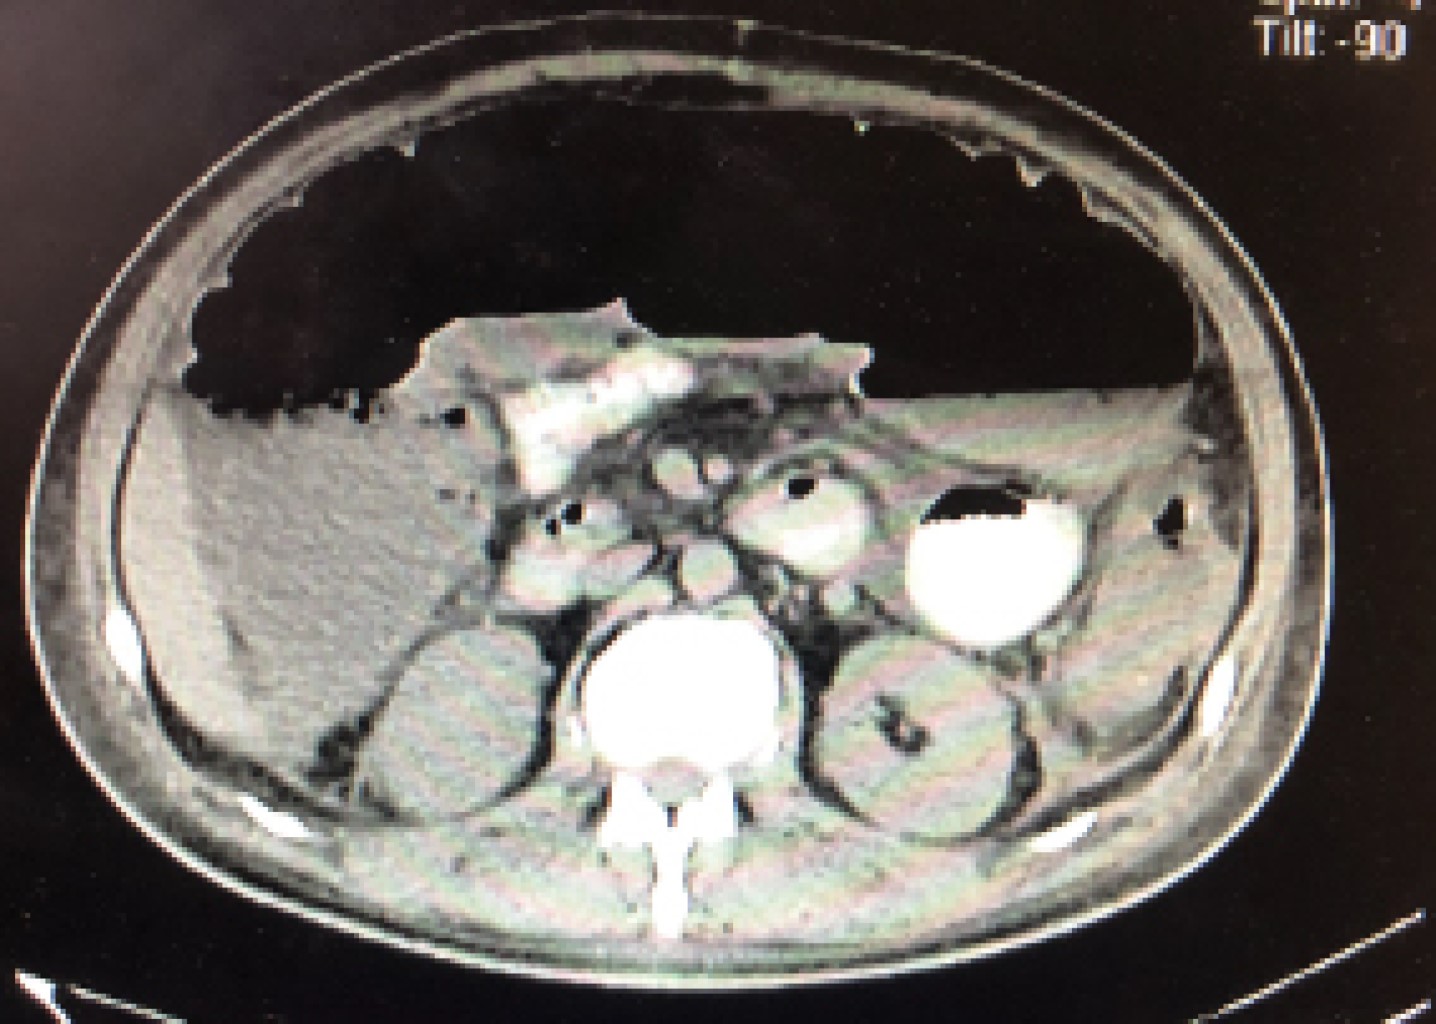

Figure 3